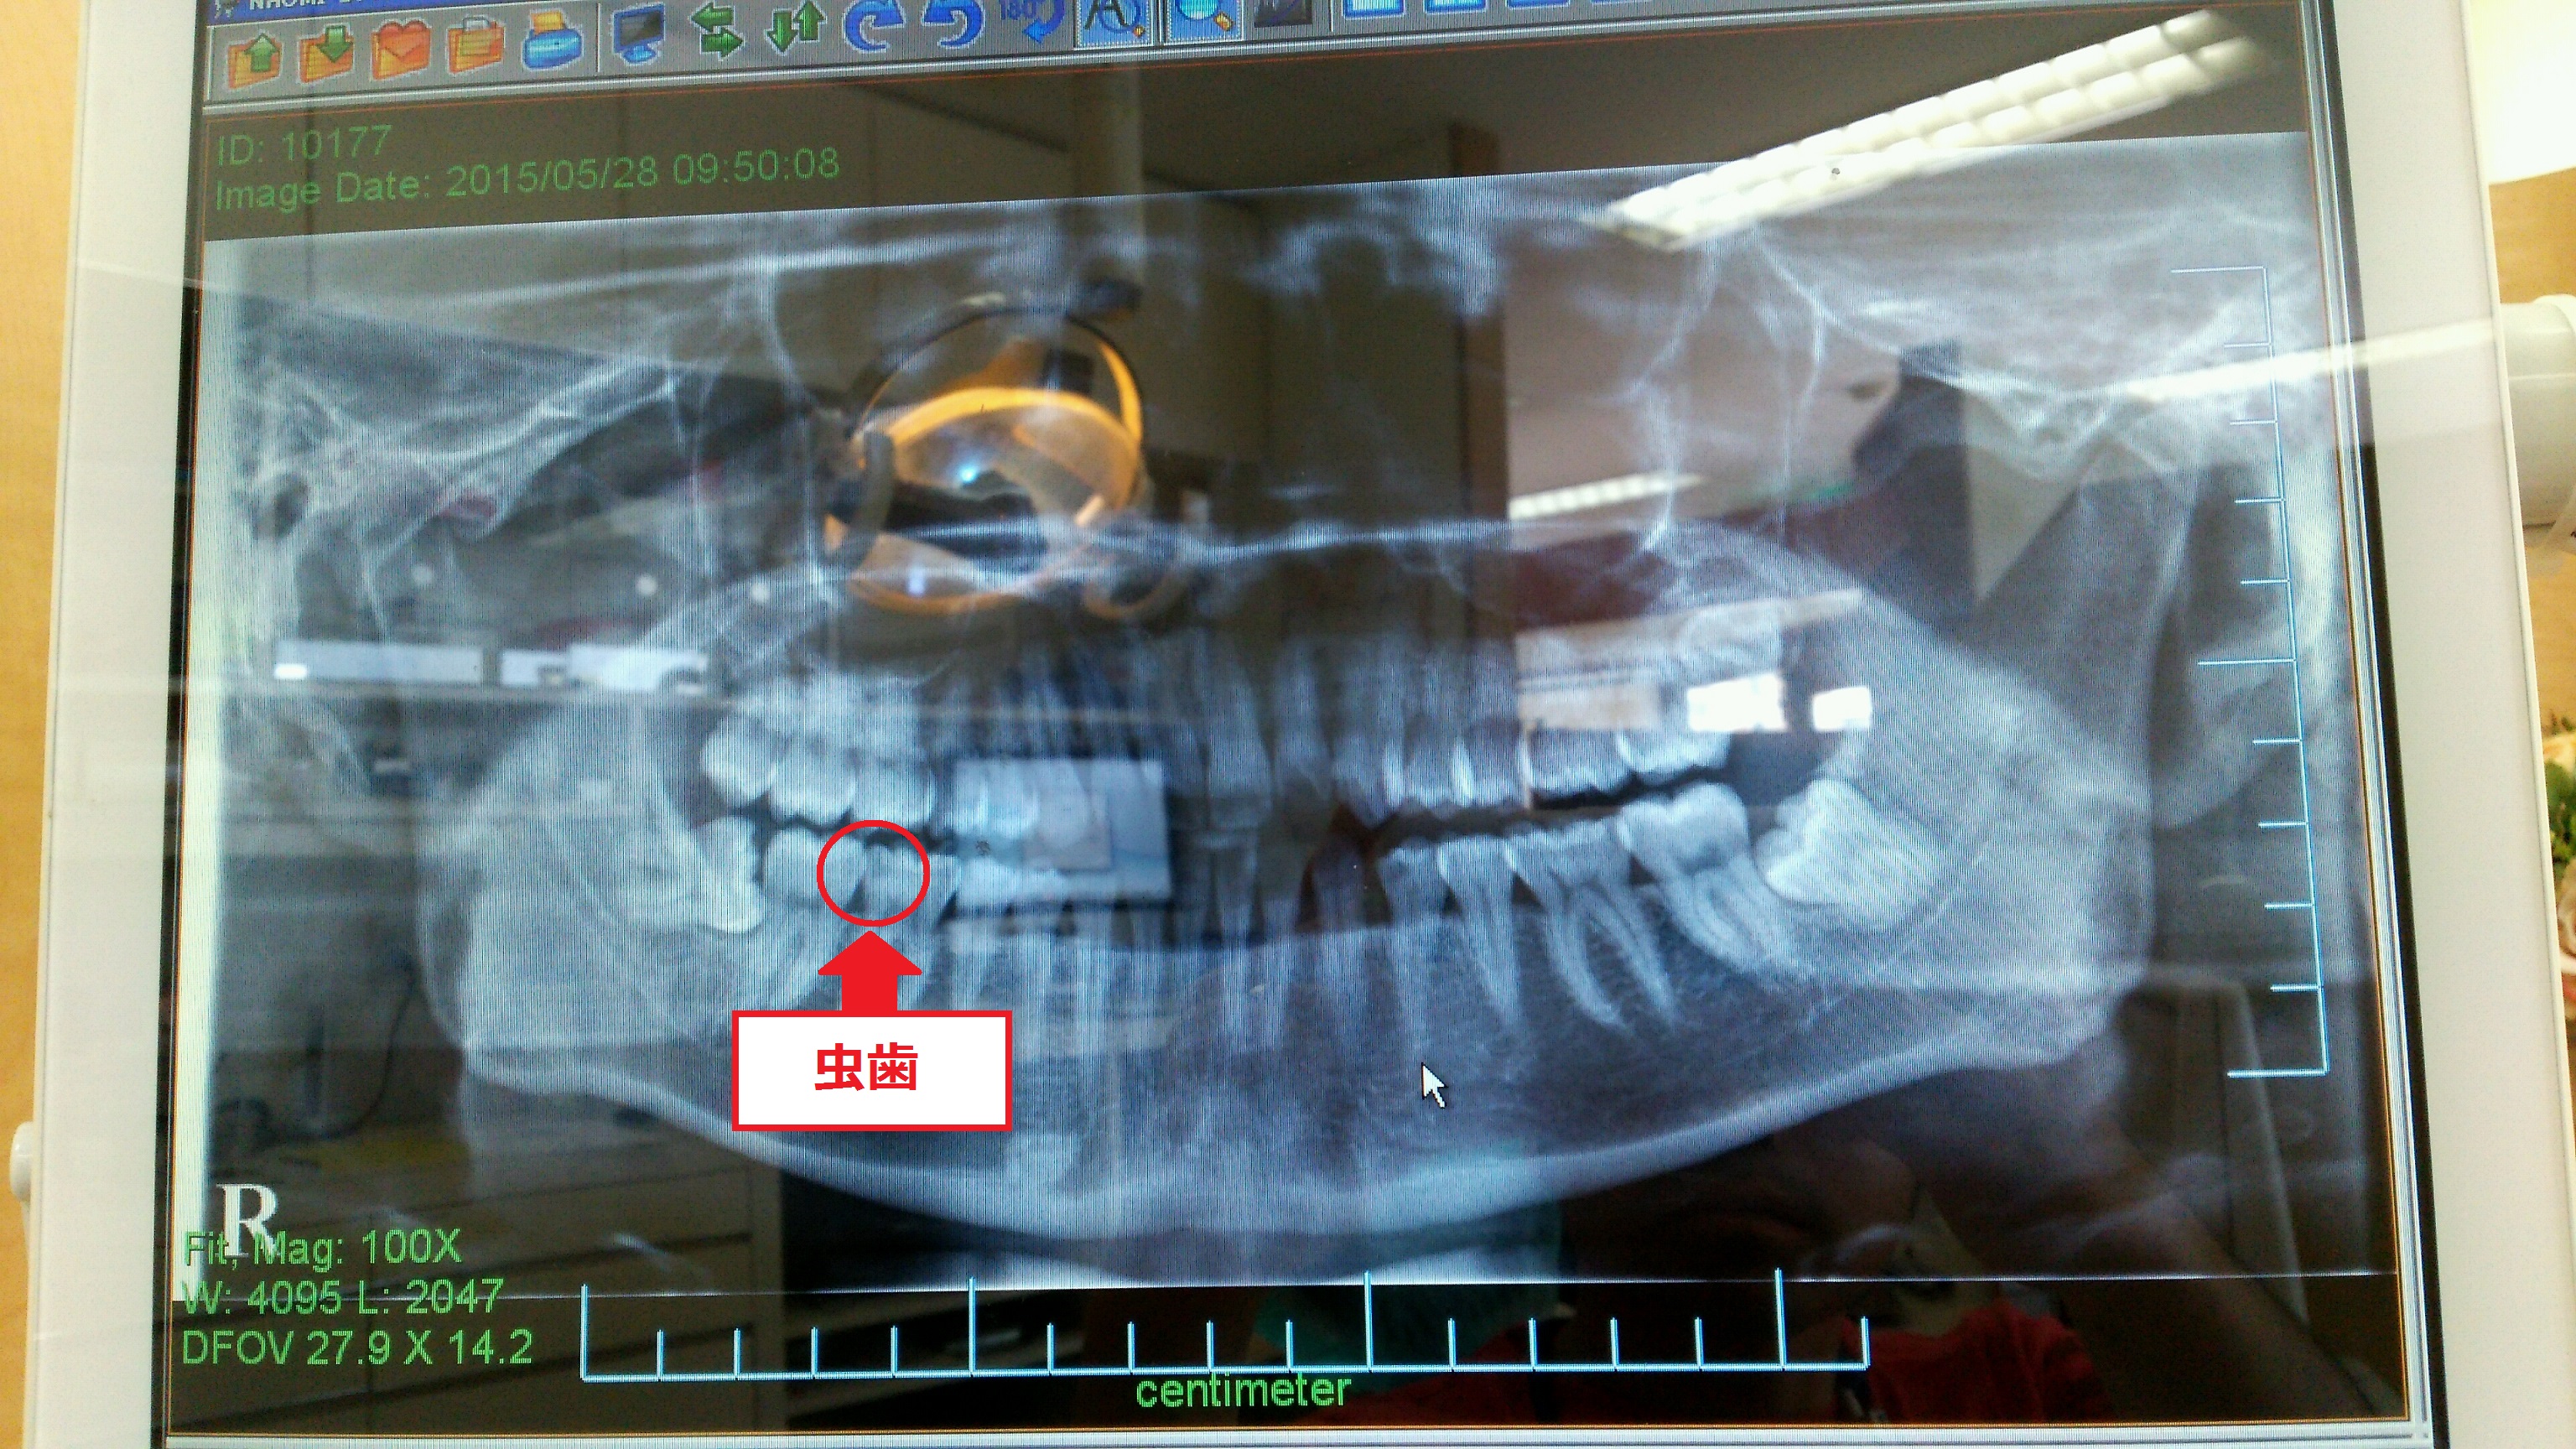

中に入って治療を始めてもらうと、やはり虫歯が(´エ`;)

虫歯が見つかったので、この後は麻酔を打たれ、歯を削られました。